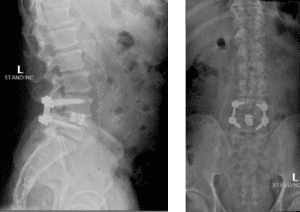

His MRI lumbar spine showed a herniated disc at L2/L3 and a grade 1 spondylolisthesis at L4/L5. Both of these findings were contributing to the patients back and leg pain.

Image 3. Post-op x-rays that show L4/L5 transforaminal lumbar interbody fusion (TLIF). There was also removal the L2/L3 disc herniation but no need for instrumentation.